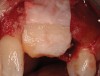

Figure 18  (Case 2) New implant in place 6 months after graft.

Figure 19  (Case 2) Allograft soft tissue placed at time of implant installation.